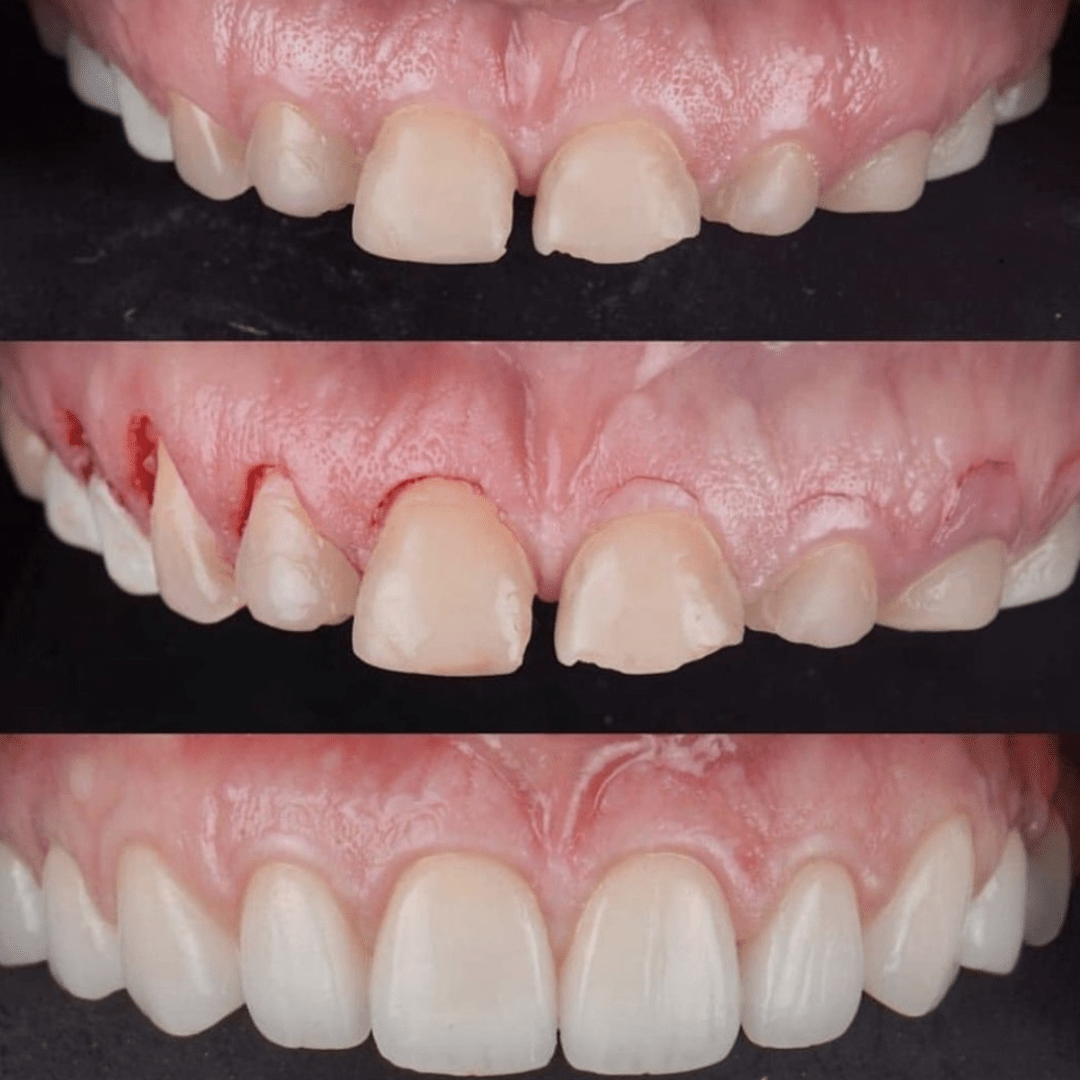

Patient presented to the clinic with the concern about the way smile looked. A thorough aesthetic analysis was done and it was decided that the patient needed bigger teeth and gum contouring to compliment the facial anatomy.